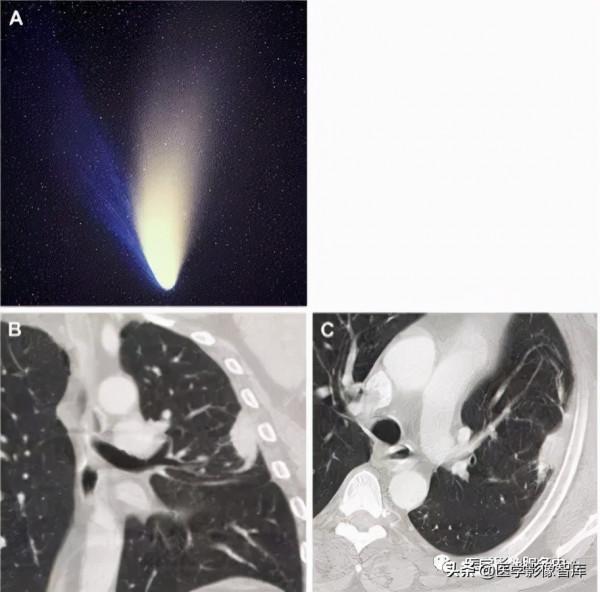

圖9.彗星尾徵 A彗星圖⽚,B和C為⼴基底與胸膜接觸圓弧狀陰影,彗星尾指向肺⻔

彗星尾徵:彗星尾徵是典型的盤形肺不張。它由圓弧樣陰影構成,起源於胸膜向同側⻔延伸,類似彗星尾巴(圖9A),由⾎管和相鄰的⽓道組成,這些⾎管和⽓道被拉⼊塌陷的肺組織,鄰近的胸膜增厚在CT上也可以看到(圖9B、9C)。盤形肺不張是良性的,不需要特殊的治療,通常體積縮⼩,偶爾會⾃⾏消退,主要的鑑別診斷包括⽀⽓管肺癌。